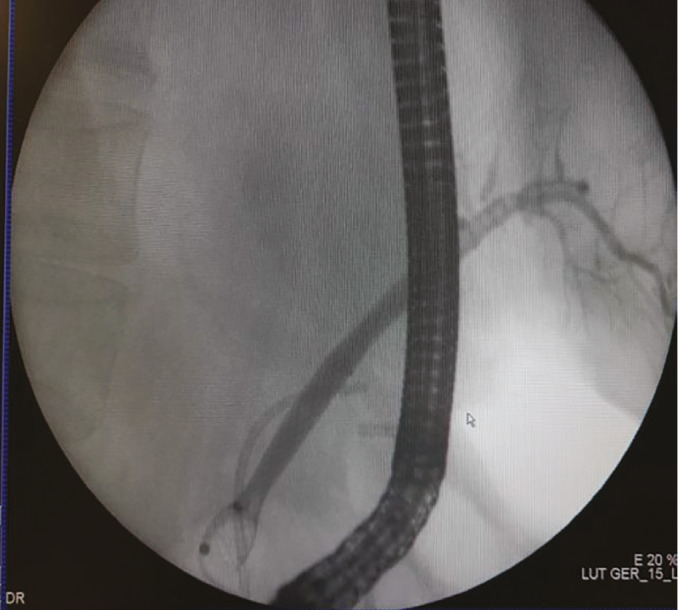

Abstract Image